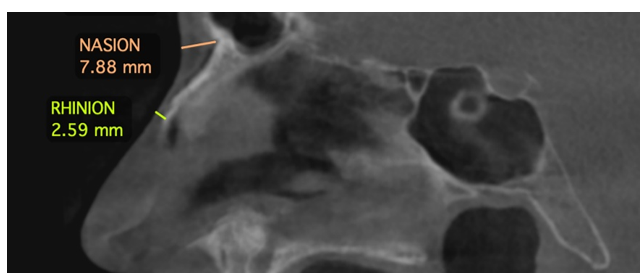

5- Rhinion (Rh): The most inferior point where the right and left nasal bones meet, essentially marking the junction between the bony and cartilaginous portions of the nasal structure in the midline (Figure-2).

Figure 2. Reference anthropological hard tissue landmarks.